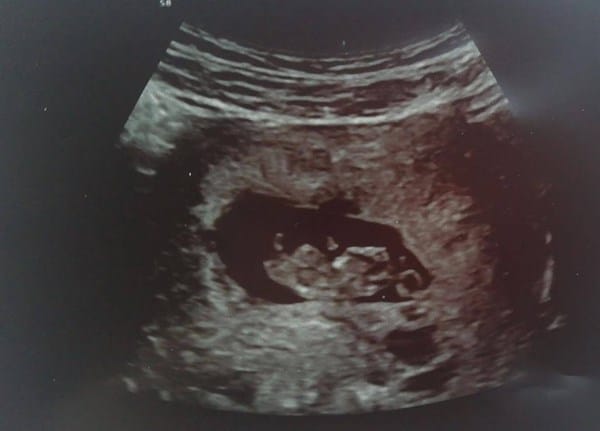

GinecologíaSer padres Anónimo el 17 jun. 21 Según la ecografía, ¿Es niño o niña? Según la ecografía, ¿alguien puede decirme si es niño o niña? Gracias. Seguir Siguiendo Dejar de seguir